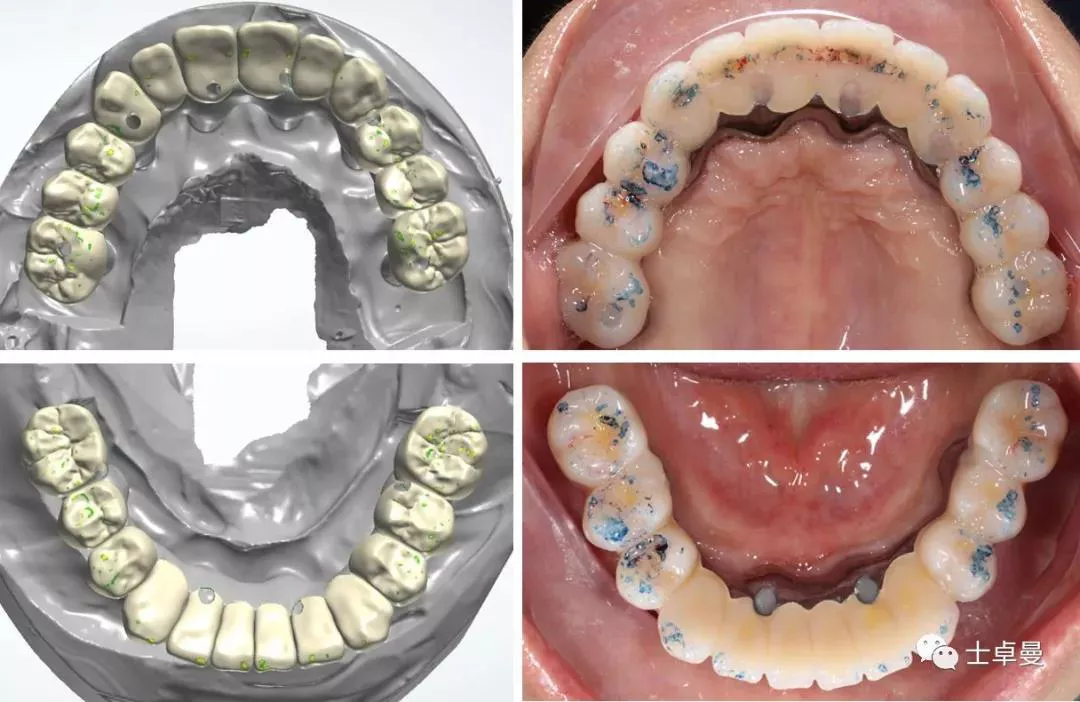

· 通过面部和口内相的重叠进行数字化微笑设计,以此指导虚拟排牙;

· 最后根据排牙信息和颌骨的骨量确定种植体的位置和型号。

· 制作牙支持固位钉导板,固位钉支持种植导板,以及固位钉辅助就位的临时修复体;

· 以期利用牙支持式导板的高精确性完成全程引导下的种植手术。